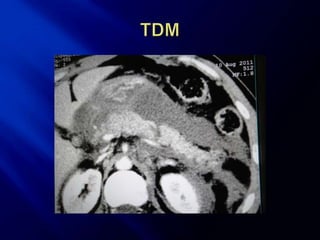

Tète du pancréas   Epanchement ACE

Epanchement

Queue du pancréas

 Rupture   du corps du

pancréas nette avec

épanchement dans

l’arrière cavité des

épiploons

 Classe III de Lucas